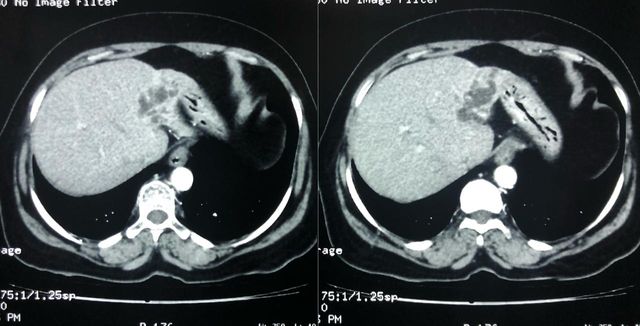

Interesting Images March 2019 : Patient came with an early stage carcinoma rectum, underwent Hemicolectomy surgery then lost to follow-up. Later after 9 month patients presented to us with Stage 4 disease (Carcinoma colon with Liver secondaries). Then we started her on treatment with Chemotherapy along with Monoclonal antibodies with six cycle of above said treatment patient achieved near complete remission. We could achieve very good results with chemotherapy even in patients with Stage 4 disease (Carcinoma colon with Liver secondaries).